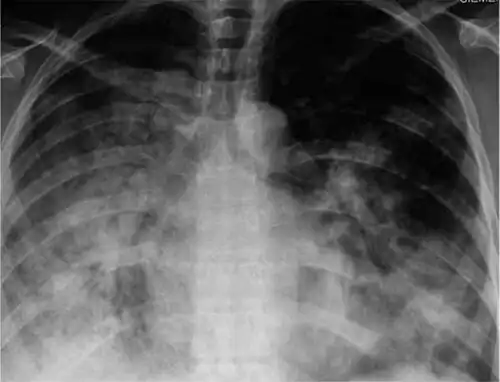

Symptomatic infections are usually mild and limited to the upper respiratory tract, but progression to pneumonia is relatively common. Pneumonia may be caused by the primary viral infection or a secondary bacterial infection. Primary pneumonia is characterized by rapid progression of fever, cough, labored breathing, and low oxygen levels that cause bluish skin. It is especially common among those who have an underlying cardiovascular disease such as rheumatic heart disease. Secondary pneumonia typically has a period of improvement in symptoms for one to three weeks[15] followed by recurrent fever, sputum production, and fluid buildup in the lungs,[8] but can also occur just a few days after influenza symptoms appear.[15] About a third of primary pneumonia cases are followed by secondary pneumonia, which is most frequently caused by the bacteria Streptococcus pneumoniae and Staphylococcus aureus.[7][8]